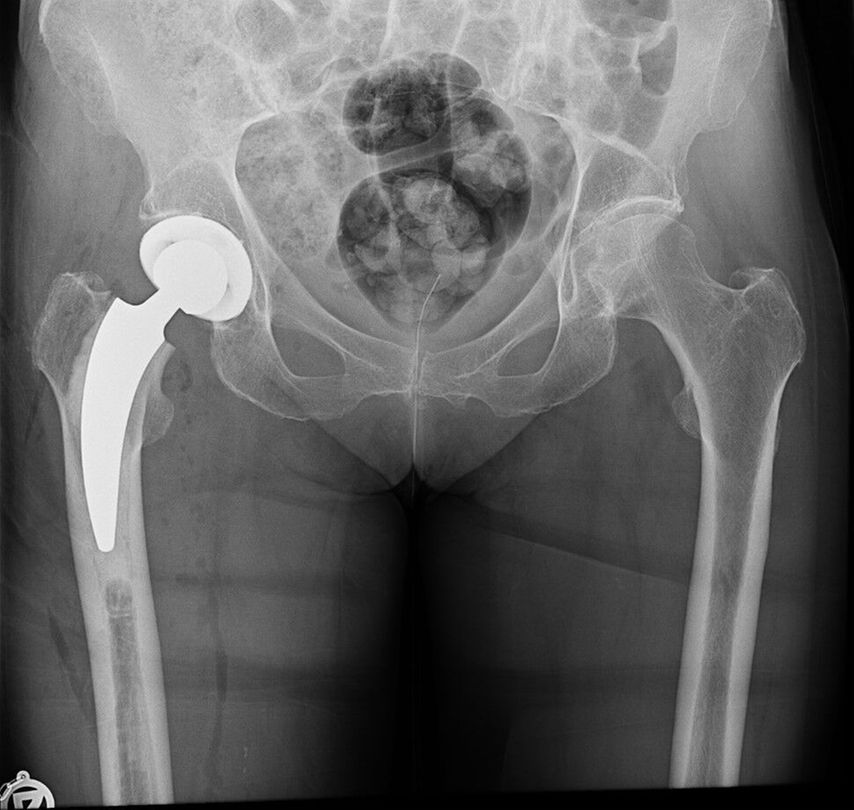

Seit 2021 werden in der Klinik für Unfallchirurgie und Orthopädie des Johannes Wesling Klinikums, Minden, ältere Patienten, die sich eine dislozierte mediale Schenkelhalsfraktur Garden III oder IV zugezogen haben, mit einer zementierten Kurzschaftprothese versorgt. Als Kopf wird entweder eine unipolare Pfanne oder eine zementfreie Pfanne implantiert. 2023 und 2024 wurde bei insgesamt 174 Patienten eine zementierte Kurzschaftprothese über einen Watson-Jones-Zugang in Rückenlage implantiert. Das Durchschnittsalter lag über 80 Jahre. Es wurden mehr Frauen als Männer behandelt (67,2% weiblich, 32,8% männlich). Fast 70% der Patienten fielen in die ASA-Klassifikation Grad 3 (1,1% ASA 1; 21,3% ASA 2; 70,1% ASA 3; 6,9% ASA 4; 0,6% ASA 5). Insgesamt 84,5% der Patienten erhielten eine Hemiendoprothese, während 15,5% mit einer Totalendoprothese versorgt wurden (Abb. 3,4). Nach der postoperativen unfallchirurgischen Behandlung wurden die Patienten entweder in eine geriatrische Klinik innerhalb oder ausserhalb des Krankenhauses verlegt oder es erfolgte eine stationäre Anschlussrehabilitation. Bis zum Zeitpunkt der Entlassung musste bei vier Patienten aufgrund einer prolongierten Wundsekretion eine Wundrevision durchgeführt werden. Im Rahmen der postoperativen Mobilisation kam es bei einem Patienten zu einer Luxation, die nach Reposition konservativ behandelt wurde. Die operierten Patienten werden aktuell zur Nachuntersuchung eingeladen.

Abb. 3: 81-jährige Patientin mit nach Sturz dislozierter Schenkelhalsfraktur Garden IV rechts